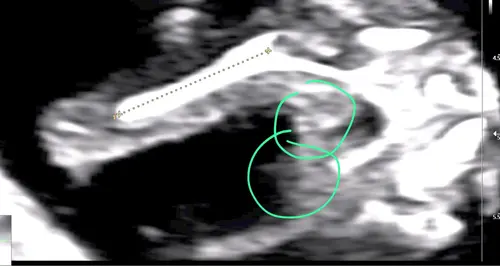

Weten jullie naar welke cirkel ik moet kijken? Dit is een 13,2 weken echo (tussen de beentjes) Bovenste lijken 2 streepjes van een meisje en daar onder lijkt een piemeltje.

Ik had bij mijn echo ook zo’n streep waardoor ik denk een jongen, maar als ik dan pottyshot foto’s zie van andere babies bij dezelfde termijn dan is het toch echt bij andere al beter te zien als het een jongen is.

Dus ik ben bang dat je nog een aantal weken moet wachten tot je zekerheid hebt 😅. Ga je een geslachtsbepalingsecho doen?